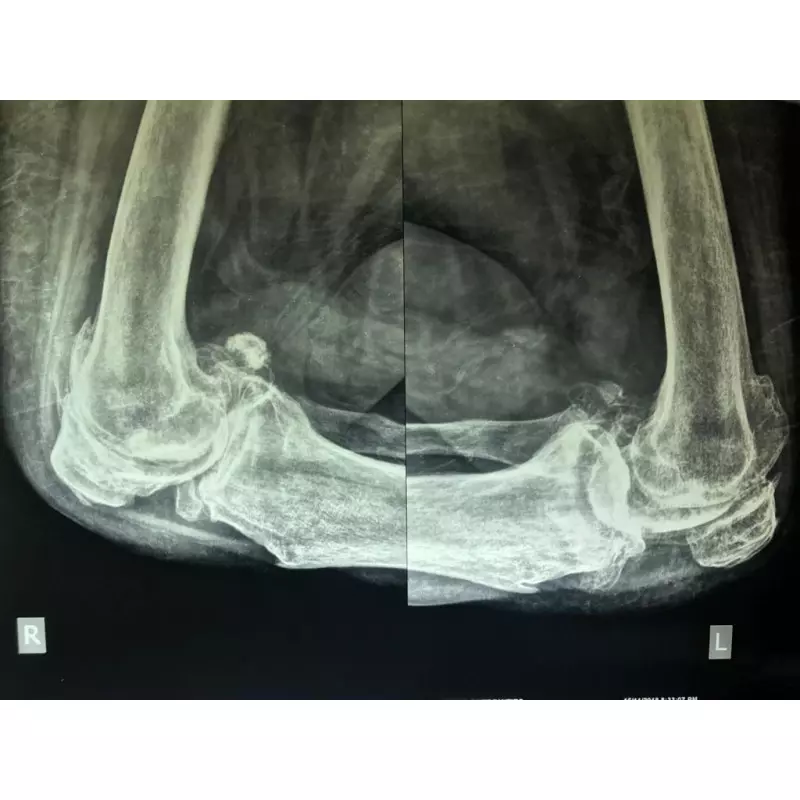

Details of Single Sitting Total Hip And Knee Replacement F/75 Obese

Supported by modern medical infrastructure and clinical excellence, we offer specialized joint replacement treatment in Asarwa. This service covers knee, hip, and other major joint procedures aimed at reducing chronic discomfort and enhancing flexibility. The treatment pathway includes accurate diagnosis, minimally invasive surgical methods where suitable, and guided physiotherapy programs to encourage lasting functional improvement.